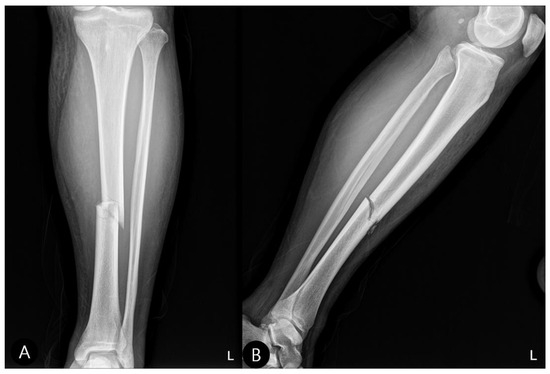

- Concomitant Injury Management:The tibial shaft fracture was subsequently stabilized with an antegrade intramedullary nail (Figure 6).